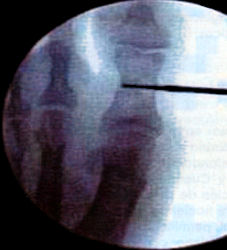

Osteotomies in the 1st metatarsal can be distal metatarsal osteotomy such as the ReverdinIsham with a medial wedge respecting the lateral cortex and performing an Osteoclasis to correct the PASA and we can also perform a modification of this osteotomy by completing it and sliding the metatarsal head laterally thereby increasing the relative closure of the 1st intermetatarsal angle. Next we can do a proximal metatarsal osteotomy performed with a wedge osteotomy proximal laterally to close the intermetatarsal angle. Another procedure that we can perform is an abductor release which is a Modified McBride. The next procedure we can do is also an osteotomy of the base of the proximal phalanx (Akin).

Hallux valgus in a young patient with intermetatarsal angle less than 20 degrees and PASA more than 8 degrees. The treatment would be exostectomy, osteotomy distal, ex., Reverdin Isham, tenotomy of the abductor and if the DASA is elevated then an osteotomy at the base of the proximal phalanx (Akin).

If we have a patient that is young with a intermetatarsal angle more than 20 degrees, PASA more than 8 degrees the protocol would be exostectomy, tenotomy of the abductor, osteotomy distal Reverdin Isham (and metatarsal base osteotomy) and with an elevated DASA we would do an Akin procedure at the base of the proximal phalanx.

If the patient is more than 45 or 50 years and has an intermetatarsal angle less than 20 degrees or greater than 20 degrees if the patient is sedentary, we would do an exostectomy, an osteotomy of the distal metatarsal, ex., Reverdin Isham, tenotomy of the abductor, and if the DASA is elevated then we would do an Akin osteotomy.

If the patient is 45 to 50 years of age and is an athlete or is very active and has an intermetatarsal angle greater than 20 degrees, we would perform an exostectomy, an osteotomy of the distal metatarsal to correct the PASA, ex., Reverdin Isham, an osteotomy at the base of the 1st metatarsal, abductor tendon release and if the DASA is elevated we would do an Akin procedure.

If the patient is elderly and has an intermetatarsal angle less than 20 degrees, we would perform an exostectomy, an osteotomy of the distal phalanx of the 1st metatarsal Reverdin Isham, an abductor tenotomy, and if the DASA is elevated then we would do an osteotomy of the proximal phalanx, an Akin procedure.

If we have an elderly patient with intermetatarsal angle greater than 20 degrees, we would do an exostectomy, an abductor tenotomy, an osteotomy of the 1st metatarsal distal and after a Reverdin Isham Modified and if the DASA is elevated then an Akin procedure would be performed.